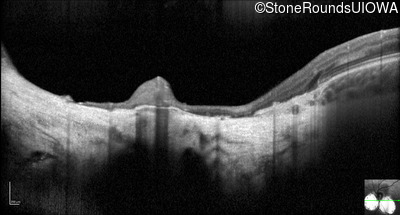

Optical Coherence Tomography - Right - 20/40 +2

Exemplar / OCT Stack